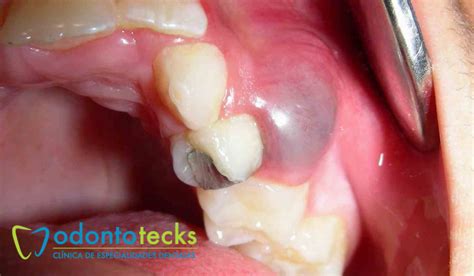

Los quistes en los dientes reciben el nombre profesional de quistes odontogénicos. Se trata de unas cavidades que suelen ser una extensión de una infección que se ha producido en los dientes o huesos adyacentes.

En su interior, están formados por pus, que es un material que puede estar en estado semisólido o también en estado líquido.

Esta clase de quistes se forma debido a la retención de una pieza dental en el momento de su erupción. Este quiste dental aparece a causa de alguna infección bucodental, como puede ser la periodontitis.

Aunque también factores como un traumatismo o una simple caries pueden derivar en la aparición de este quiste dental. Son los que se encuentran en la raíz de los dientes.

Lo cierto es que el inicio de un quiste no suele provocar graves molestias. En algunos casos, el paciente únicamente detecta la presencia de un bulto en la encía.